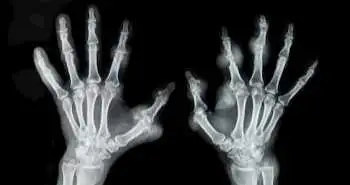

Использование ПЭТ/КТ с фторидом натрия F-18 для оценки активности ревматоидного артрита

Данное проспективное диагностическое исследование посвящено изучению клинической эффективности использования метода ПЭТ/КТ F -18 NaF для оценки активности РА.

У пациентов с диагностированным ревматоидным артритом (РА) и синовиитом отмечалось более интенсивное поглощение фторида натрия F-18 (NaF) суставами по сравнению с суставами без синовиита. Таким образом, установлена эффективность использования метода позитронно-эмиссионной томографии / компьютерной томографии (ПЭТ/КТ) с F-18 NaF в качестве метода визуализации при проведении оценки активности РА.

В исследовании приняли участие 17 пациентов с РА. Кроме физикального осмотра, анализа крови и ультразвукового исследования, участникам проводили ПЭТ/КТ с F-18 NaF. Для каждого из 28 болезненных суставов, оцененных с помощью индекса активности заболевания на основе оценки 28 суставов с учетом уровня оседания эритроцитов (DAS28CRP), рассчитали стандартизированный уровень накопления вещества суставами, а также соотношение поглощения вещества суставом и костной тканью.

У болезненных суставов с отеком и без него стандартизированный уровень накопления (СУН) был статистически значимо выше, как и соотношение поглощения вещества суставом и костной тканью, по сравнению с суставами без синовиита (см. таблицу ниже).

Общий коэффициент поглощения вещества тканью суставов и суммарное соотношение поглощения вещества суставами и костной тканью на основании данных, полученных при исследовании 28 суставов, выявило сильную положительную связь со значениями индекса DAS28-ESR. Была выявлена статистически значимая положительная корреляция между суммарным значением СУН суставами и результатами ультразвукового исследования.

Согласно стандартизированному уровню накопления суставами, чувствительность метода при прогнозировании синовиита составила 83,2 %, а специфичность – 92,7 %, в то время как для соотношения поглощения вещества суставами и костной тканью чувствительность и специфичность составили 81,5 % и 90,7 % соответственно. Совокупность обоих ограничений ПЭТ/КТ 28 суставов выявила 100 % диагностическую точность в отношении высокой активности РА.

Выявлена выраженная положительная связь междуобщим поглощением вещества суставами и значениями индекса DAS28-ESR, которая позволяет сделать точный прогноз в отношении высокой активности заболевания.